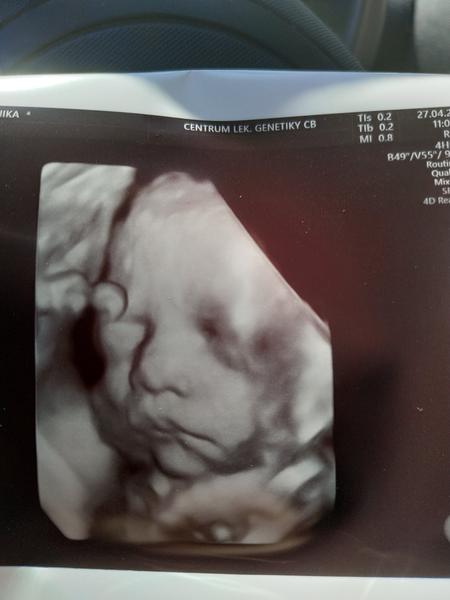

Ve 26-28.tt s obouma synama jsem byla cca v gennetu ☺️A za me parada ..u prvnihu tehu me diky tomu konecne nekdo rekl co čekame 😂